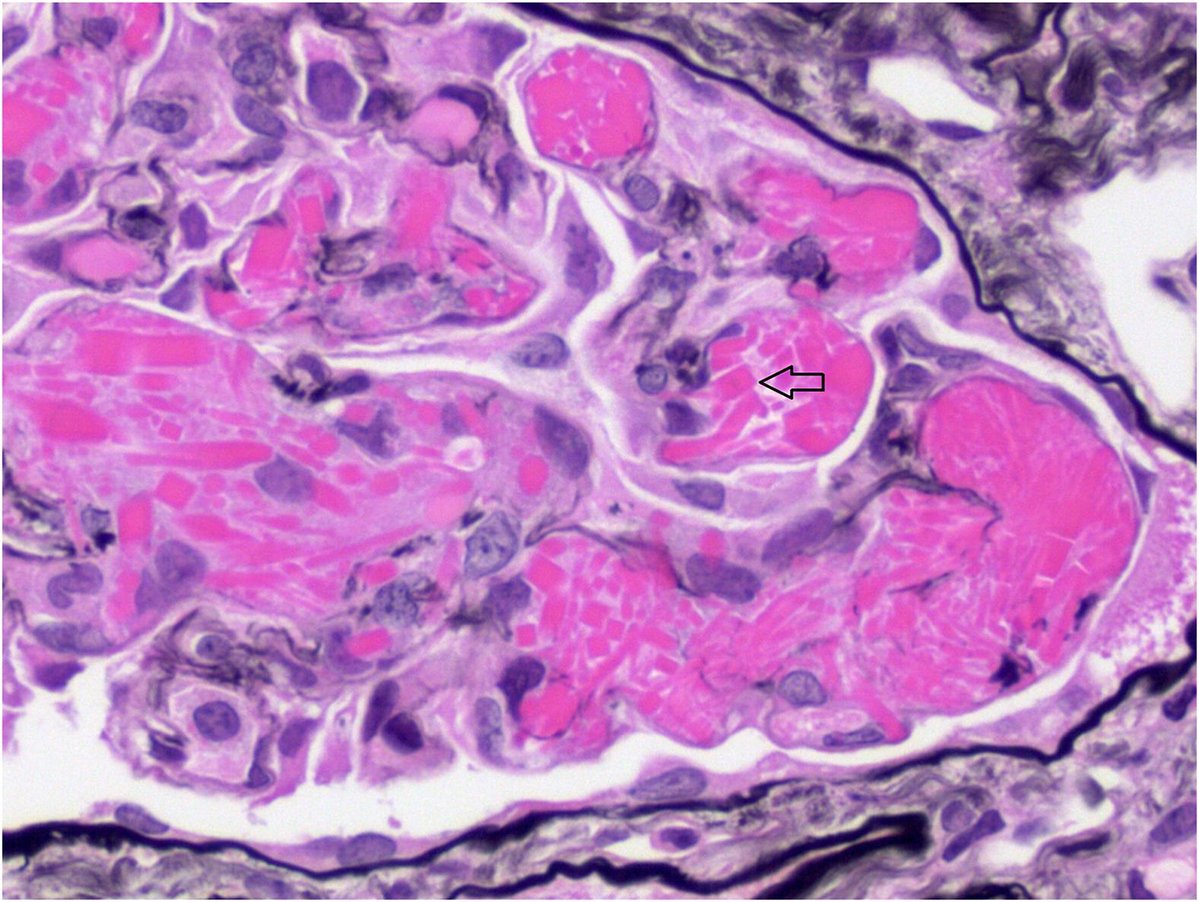

This biopsy shows the characteristic features of uric acid nephropathy (commonly known as gout), which results from precipitation of uric acid in the kidney parenchyma. Tophi frequently occur in the medulla, and usually consist of central regions of acellular, granular material